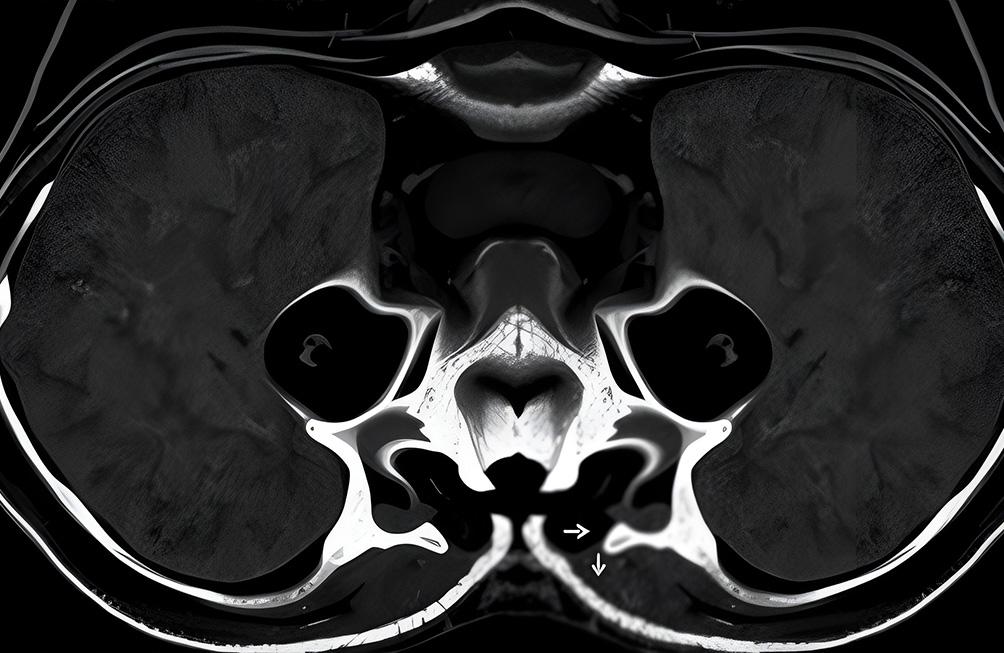

L'IRM pelvienne est une technique non invasive, qui permet d'examiner en détail la région pelvienne. Cet examen est un outil très précieux car elle offre une excellente résolution des tissus mous, permettant aux médecins de poser un diagnostic précis et de planifier au mieux le traitement.

- Étude des voies urinaires et des organes urinaires, en cas de suspicion de pathologies ou de malformations.